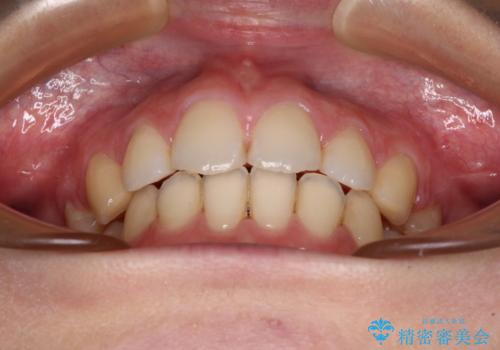

- 口元の突出感と口の閉じにくさを気にして来院された患者様です。

上下左右第一小臼歯4本を抜歯し、ワイヤー装置にて口元を引っ込めるよう矯正治療を行うこととしました。

ご友人などがびっくりするほど口元の突出感を改善することができ、患者様には大変満足していただきました。